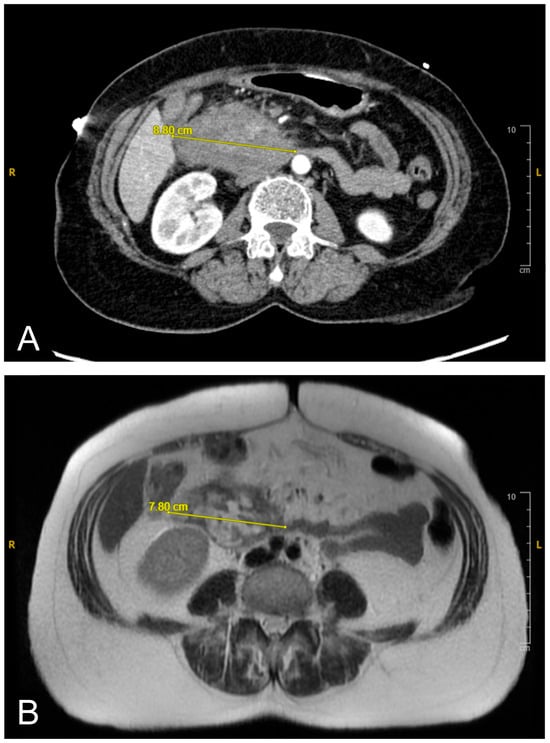

A CT scan of the abdomen revealed a heterogeneous lesion measuring 6.1 cm × 8.8 cm × 8.7 cm in the second portion of the duodenum with mild heterogeneous enhancement (Figure 1A). Given the imaging features, a duodenal malignancy was initially suspected. The attending physician decided to pursue further investigations to rule out malignancy, and the patient was admitted for a comprehensive evaluation to establish a definitive diagnosis. The following day, an MRI cholangiogram with contrast was performed, revealing a lesion measuring 7.8 cm × 5.8 cm, in the second and third parts of the duodenum. The lesion exhibited heterogeneity with a lack of enhancement, indicative of a duodenal hematoma (Figure 1B). The hematoma affected the duodenum and the head of the pancreas, likely causing extrinsic compression with mild bile duct dilation.

Figure 1. (A): Initial contrast-enhanced abdominal CT scan revealing duodenal hematoma measuring 8.8 cm in its widest diameter. (B): Follow-up MRI cholangiogram showing interval regression in size to 7.8 cm. Image quality was limited by motion artifact.